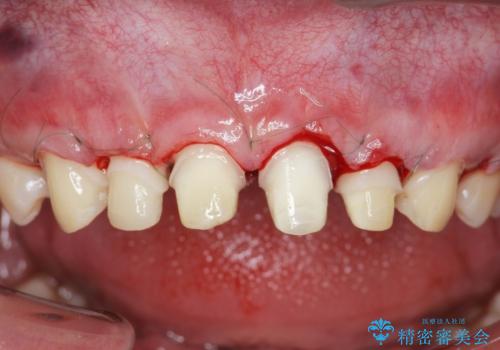

- 「前歯の見た目、歯ぐきの腫れを改善したい。」と希望され来院されました。

前歯には接着性の維持装置や、中途半端な形の連結クラウンが装着され、清掃性が悪く歯ぐきの腫れや、歯ぐきの形態の不揃いが認められました。

ただ、白いオールセラミッククラウンを製作・装着するのではなく、将来にわたり安定した状況を獲得するため、歯周外科を行い歯ぐきと周囲の歯槽骨の形態を整えていきます。

歯周外科を行ったことで、歯ぐきの形態や腫れが改善され、審美性だけでなく清掃性も大きく改善することができました。